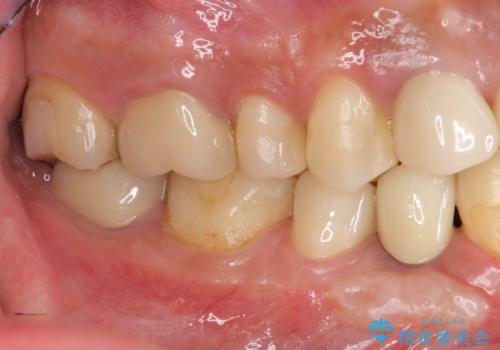

- 長年虫歯の治療を受け続けたことで銀歯・コンポジットレジン修復だらけになってしまい、今後の見た目や歯を大切にするためにセラミック治療矯正治療を希望され来院されました。

マイクロスコープを用いた精密根管治療やセラミック治療、マウスピース矯正治療を一つの医院で行うことのできる当法人ならではの総合歯科治療を実践していきます。

歯並びを整えたことで、歯ブラシのしやすさが向上し見た目も銀歯を全て除去したことで大きく改善して大変満足いただくことができました。